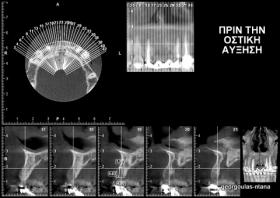

ΤΟΠΟΘΕΤΗΣΗ ΕΜΦΥΤΕΥΜΑΤΩΝ ΣΤΗΝ ΠΕΡΙΟΧΗ ΤΩΝ ΑΝΩ ΤΟΜΕΩΝ

Στην ασθενή αυτή είχαν πραγματοποιηθεί 2 ενδοδοντικές θεραπείες (απονευρώσεις) που ακολουθήθηκαν από 2 ακρορριζεκτομές χωρίς επιτυχία. Η ασθενής ήταν δυσαρεστημένη με την όψη κ το χρώμα των δύο δοντιών και φυσικά με το πρόβλημα υγείας που δημιουργήθηκε. Πραγματοποιήθηκε εξαγωγή των δύο δοντιών, οστική αύξηση και τοποθέτηση 2 εμφυτευμάτων στις θέσεις των δύο κεντρικών τομέων. Τα δύο εμφυτεύματα αποκαταστάθηκαν με 2 υβριδικά κολοβώματα από διπυριτικό λίθιο και ολοκεραμικές στεφάνες ενώ στους 2 πλάγιους τομείς τοποθετήθηκαν επίσης ολοκεραμικές στεφάνες.